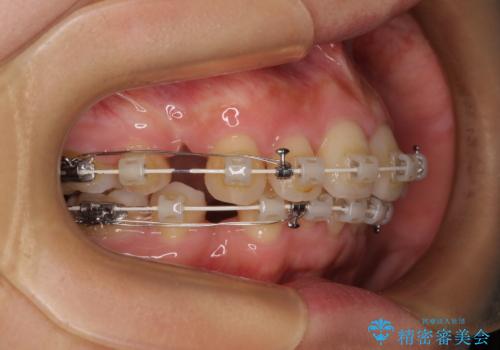

- 矯正装置

- 審美装置

- 奥歯も含めて全体的なデコボコと前歯の突出感を気にして来院された患者様です。

上下左右第一小臼歯4本を抜歯し、ワイヤー装置にて矯正治療を行うこととしました。

想像以上に咬合力が強く、抜歯したスペースを閉じきるまでに長期間を要することとなりました。

前歯の突出感がなくなり、仕上がりには大変満足していただけました。